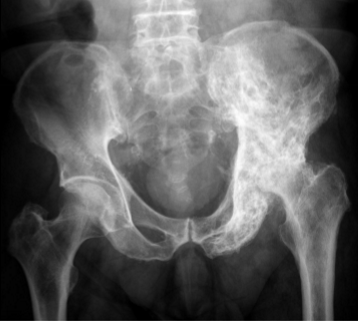

radiology - pelvis

most common avulsion fractures location